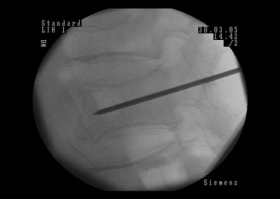

当院でのPVPの流れ